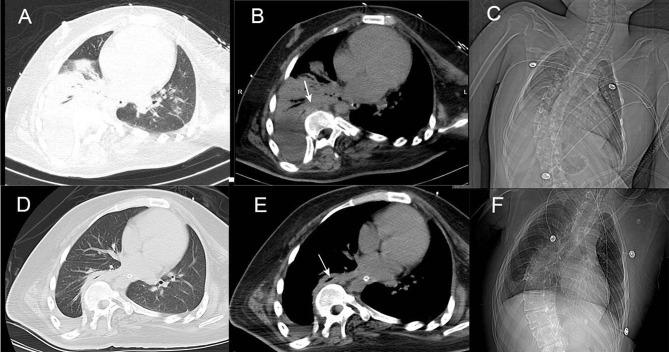

We report a rare case of a young, non-immunocompromised man with cerebral palsy, spinal deformity, and pulmonary infection. The patient's condition improved after treatment with voriconazole and became stable.

我们报告一例罕见病例,患者为一名患有脑瘫、脊柱畸形和肺部感染的年轻非免疫功能低下男性。患者接受伏立康唑治疗后病情改善并趋于稳定。